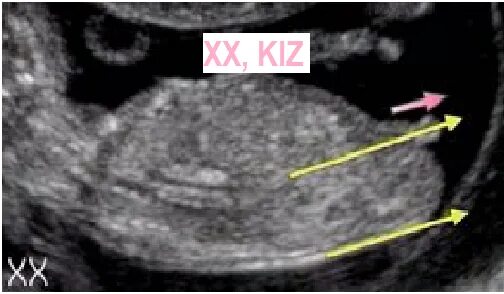

Как определить пол ребенка в 12 недель